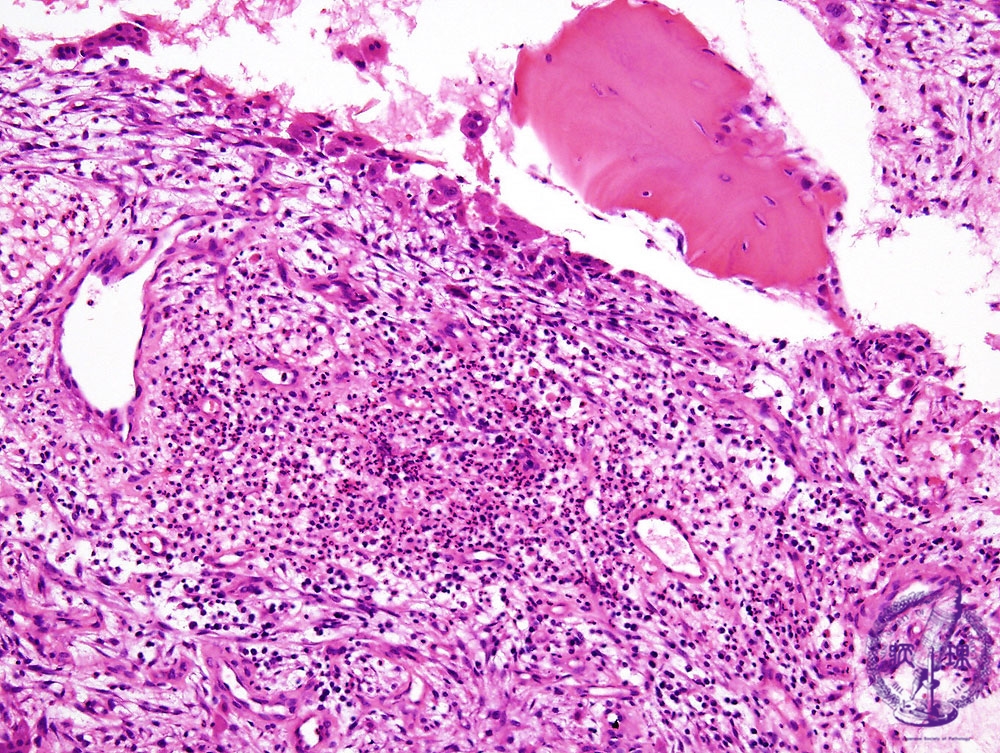

Microscopic view (HE: middle power view): Caused by bacterial infection. Significant neutrophilic infiltration is seen, with tiny bony trabeculae.